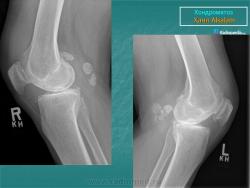

Хондроматоз внутрисуставной (синовиальный).

Хондроматоз внутрисуставной (синовиальный)